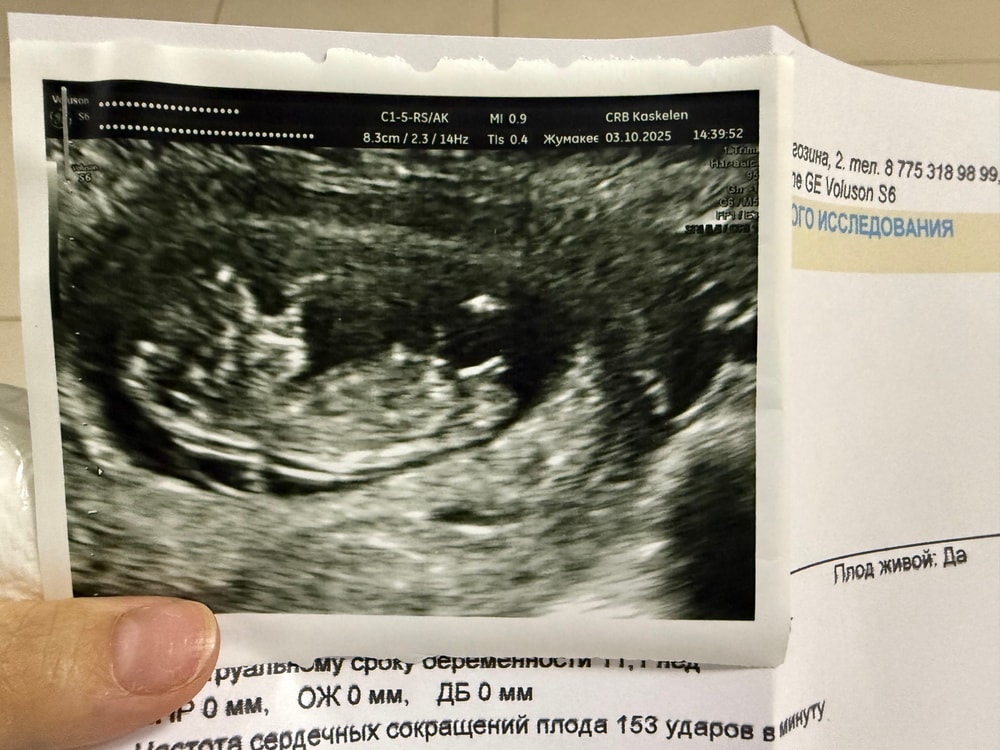

По узи 11,1 неделя

по М 10,3 недель